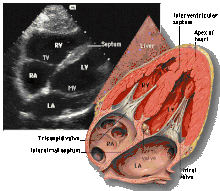

Apical four chamber (A4C)

This view is obtained at the apex of the heart and looking toward the base of the heart (where the valves are). In this view, the mitral valve, tricuspid valve, and all four chambers are visible. This view shows the right ventricle from base to apex and is a useful view to estimate RV systolic function. TAPSE (= tricuspid annular plane systolic excursion) is also measured in this view with M-mode through the lateral tricuspid annulus.

Structures:

- Inferior septum and anterior lateral segments of the left ventricle

- Right ventricle

- Left atrium

- Right atrium

- Mitral valve

- Tricuspid valve

Measurements in this view can be used to quantify the heart:

- RV size and function; TAPSE

- Left atrial size

- Right atrial size

- Mitral valve flow is best seen in this view and has the best angle with probe to estimate flows

- Tricuspid valve flow

- Tissue doppler at the mitral valve annulus (septum and lateral wall) for diastolic function

- Agitated saline bubble study for right to left shunting (PFO, ASD, VSD)

- With contrast, apical and mural LV thrombi can be easily seen